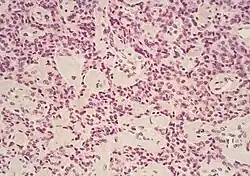

The most common form of pancreatic cancer (adenocarcinoma) is typically characterized by moderately to poorly differentiated glandular structures on microscopic examination. There is typically considerable desmoplasia or formation of a dense fibrous stroma or structural tissue consisting of a range of cell types (including myofibroblasts, macrophages, lymphocytes and mast cells) and deposited material (such as type I collagen and hyaluronic acid). This creates a tumor microenvironment that is short of blood vessels (hypovascular) and so of oxygen (tumor hypoxia).[2] It is thought that this prevents many chemotherapy drugs from reaching the tumor, as one factor making the cancer especially hard to treat.[2][3]

| Cancer type | Relative incidence[11] | Microscopy findings[11] | Micrograph | Immunohistochemistry markers[11] | Genetic alterations[11] |

| Pancreatic neuroendocrine tumor | 5% | Multiple nests of tumor cells | ![]() |

|